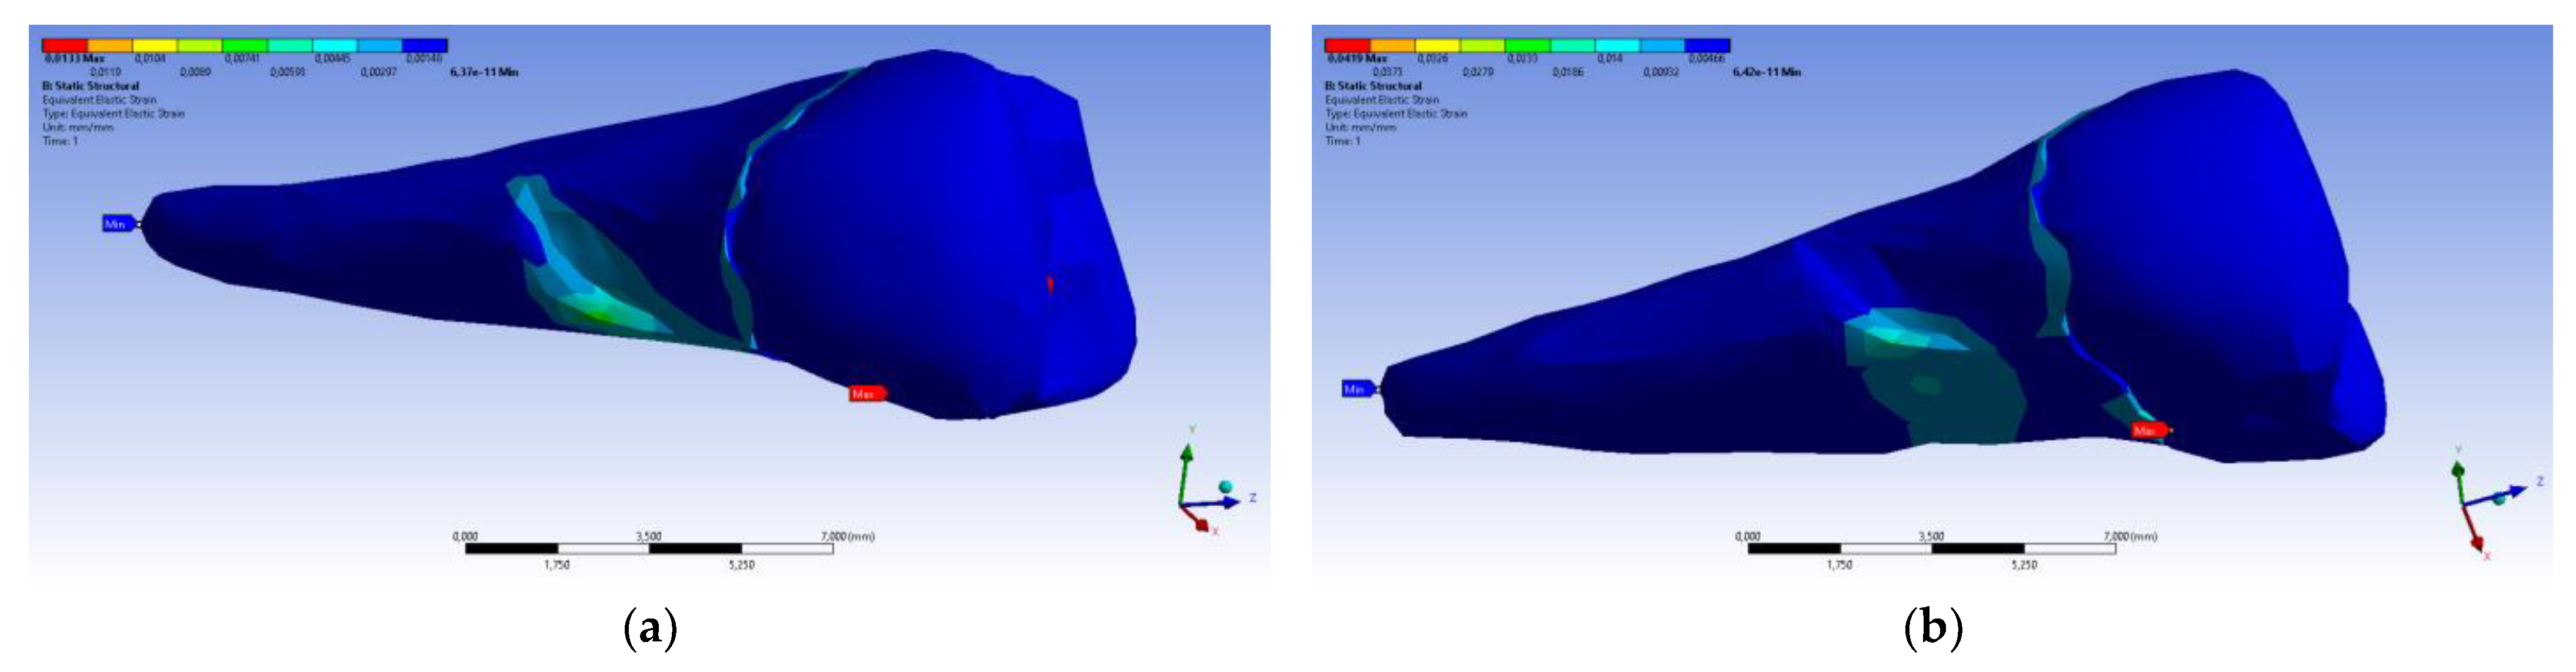

3. Finite Element Analysis (FEA) of Mandibular Right Premolars

| Maximum Tangential Stress | Main Elastic Relative Deformation | Main Maximum Elastic Relative Deformation | Main Minimum Elastic Relative Deformation | Maximum Tangential Elastic Relative Deformation | Relative elastic Normal X Deformation | Relative Elastic Normal Y Deformation | Relative Elastic Normal Z Deformation | Relative Elastic Tangential XY Deformation | Relative Elastic Tangential YZ Deformation | Relative Elastic Tangential XZ Deformation | |||

| Minimum | 5.4 × 10−7 MPa | 6.36 × 10−11 mm/mm | −1.33 × 10−5 mm/mm | −1.05 × 10−2 mm/mm | 7.6 × 10−11 mm/mm | −2.26 × 10−3 mm/mm | −1.43 × 10−3 mm/mm | −3.45 × 10−3 mm/mm | −2.81 × 10−3 mm/mm | −4.09 × 10−3 mm/mm | −7.93 × 10−3 mm/mm | ||

| Maximum | 143 MPa | 1.33 × 10−2 mm/mm | 9.66 × 10−3 mm/mm | 1.09 × 10−5 mm/mm | 2.01 × 10−2 mm/mm | 1.37 × 10−3 mm/mm | 1.89 × 10−3 mm/mm | 3.14 × 10−3 mm/mm | 6.23 × 10−3 mm/mm | 1.65 × 10−2 mm/mm | 3.13 × 10−3 mm/mm | ||

| Minim. in | Cementum | Cementum | Enamel | Cementum | Cementum | Cementum | Cementum | Cementum | Cementum | Cementum | Cementum | ||

| Maxim. in | Cementum | Cementum | Cementum | Cementum | Cementum | Cementum | Cementum | Enamel | Cementum | Cementum | Cementum |

| Maximum Tangential Stress | Main Elastic Relative Deformation | Maximum Main Elastic Relative Deformation | Minimum Main Elastic Relative Deformation | Maximum Tangential Elastic Relative Deformation | Relative Elastic in Normal X Deformation | Relative Elastic in Normal Y Defomation | Relative Elastic in Normal Z Deformation | Relative Elastic Tangential XY Deformation | Relative Elastic Tangential YZ Deformation | Relative Elastic Tangential XZ Deformation | |||

| Minimum | 5.45 × 10−7 MPa | 6.42 × 10−11 mm/mm | −1.31 × 10−5 mm/mm | −3.26 × 10−2 mm/mm | 7.68 × 10−11 mm/mm | −7.42 × 10−3 mm/mm | −5.42 × 10−3 mm/mm | −7.58 × 10−3 mm/mm | −6.29 × 10−3 mm/mm | −9.77 × 10−3 mm/mm | −2.51 × 10−2 mm/mm | ||

| Maximum | 450 MPa | 4.19 × 10−2 mm/mm | 3.08 × 10−2 mm/mm | 7.02 × 10−5 mm/mm | 6.34 × 10−2 mm/mm | 4.72 × 10−3 mm/mm | 6.75 × 10−3 mm/mm | 9.91 × 10−3 mm/mm | 1.88 × 10−2 mm/mm | 5.21 × 10−2 mm/mm | 1.11 × 10−2 mm/mm | ||

| Minim. in | Cementum | Cementum | Enamel | Cementum | Cementum | Cementum | Cementum | Cementum | Cementum | Cementum | Cementum | ||

| Maxim. in | Cementum | Cementum | Cementum | Cementum | Cementum | Cementum | Cementum | Enamel | Cementum | Cementum | Cementum |